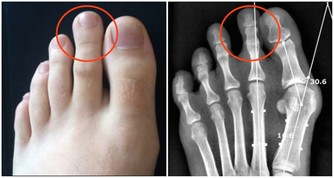

3.口腔有潰瘍出血。

因此,口腔潰瘍出血在概率上的確存在感染的可能,但被感染的機率微乎其微。

至於很多人擔心,有口腔潰瘍的情況下接吻感染,就​​算真的發生,也是因為血液暴露,歸於血液傳播,而不能說接吻是艾滋病的一個傳播途徑。